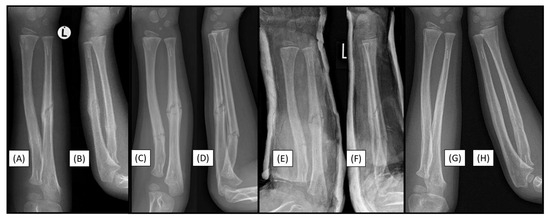

3.1. Case 1: Iatrogenic Cortex Perforation